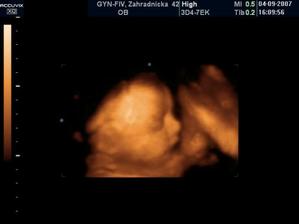

Naše srdiečko sa narodilo 9.12.2007 o 22.55 hod. Lenuška merala 49cm a vážila 3 500g. Bol to náš najšťastnejší deň v živote a ocko bol po celý čas s nami. Lenka je veľmi poslušné bábatko, stále sa smeje a maminke s ockom robí každý den kopec radosti...